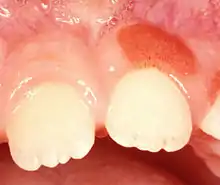

| Plasma cell gingivitis in an adult (histologically verified). | |

Plasma cell gingivitis appears as mild gingival enlargement and may extend from the free marginal gingiva on to the attached gingiva.[6] Sometimes it is blended with a marginal, plaque induced gingivitis, or it does not involve the free marginal gingiva. It may also be found as a solitude red area within the attached gingiva (pictures). In some cases the healing of a plaque-induced gingivitis or a periodontitis resolves a plasma cell gingivitis situated a few mm from the earlier plaque-infected marginal gingiva. In case of one or few solitary areas of plasma cell gingivitis, no symptoms are reported from the patient. Most often solitary entities are therefore found by the dentist.[2]

The gums are red, friable, or sometimes granular, and sometimes bleed easily if traumatised.[6] The normal stippling is lost.[7] There is not usually any loss of periodontal attachment.[6] In a few cases a sore mouth can develop, and if so pain is sometimes made worse by toothpastes, or hot or spicy food.[7] The lesions can extend to involve the palate.[7]